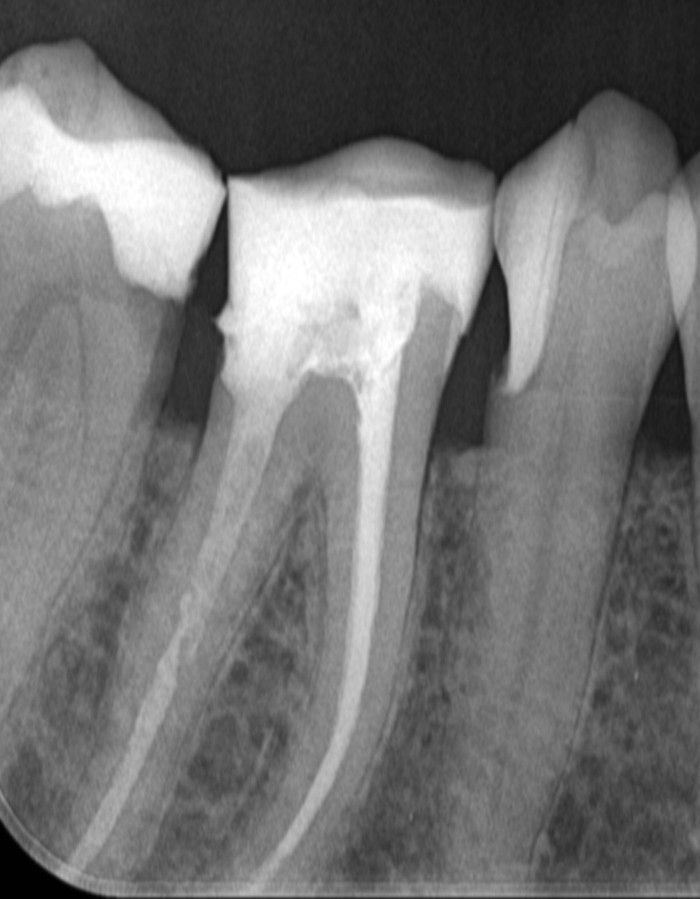

Hier een soortgelijke vraag m.b.t. een begroting voor een wortelkanaalbehandeling aan nr: 46.

In dit geval is code E17 (Wortelkanaalbehandeling vier of meer kanalen) begroot. De 46 heeft (voor zover ik weet) 2 kanalen dus kan dit kloppen?

Ook 4 maal een X10 (kleine röntgenfoto) voor de 46. M.i. nogal veel dus waarom zoveel foto's?

'de 46 heeft meestal 4 kanalen',....maar dus niet altijd. Is dat op een röntgenfoto te zien? Wanneer u wilt kan ik u eventueel in een pb een foto toesturen. Het zijn namelijk niet mijn foto's maar die van een goede kennis die ik probeer te helpen.

Op de begroting voor een geplande wortelkanaalbehandeling van de 46 staat weer 4 maal een X10 gepland voor uitsluitend dit element. Wat kan hier de reden voor zijn?

Lees goed :...Ik schreef: Heeft vaak ! 4 kanalen. Soms op een foto te zien maar vaak niet tenzij wij een naald in de kanaal steken maar dan zijn wij al met de wkb bezig.